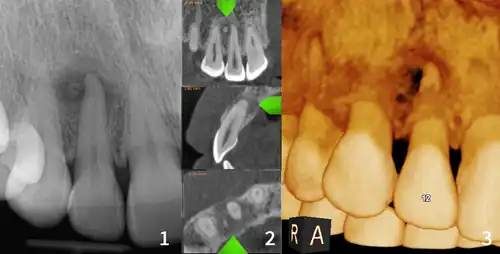

| Florid osseous dysplasia of the mandible | |

| Diagnostic method | X-ray, CBCT scan, vitality testing of teeth |

Diagnosis is based on clinical and radiographic observations, and in rare cases, biopsy may be performed.[3] Diagnosis is important so that the treating doctor does not confuse it for another periapical disease such as rarefying osteitis or condensing osteitis. Incorrect diagnosis could lead to unnecessary root canal treatments, or biopsy or surgical intervention which can be invasive and increase the risk of infection.[5] A pulp vitality test such as a cold test or electric pulp test can aid in diagnosis, since COD generally does not compromise pulp vitality.[6] COD can be found in individuals of all ages and ethnic backgrounds, but it has been observed more frequently in individuals of African, East Asian, and Asian descent.[7] Cone-beam computed tomography (CBCT) has proven useful in distinguishing between COD and periapical cysts, when examined with quantitative texture analysis using specialized software.[5]